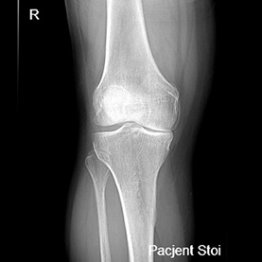

Endoproteza stawu kolanowego

Endoprotezoplastyka stawu kolanowego to skuteczna metoda leczenia zaawansowanej choroby zwyrodnieniowej kolana. Zabieg polega na chirurgicznym usunięciu uszkodzonych powierzchni stawowych i ich zastąpieniu nowoczesnym implantem – całkowitym lub częściowym – który przywraca funkcję stawu, poprawia jego stabilność i eliminuje ból. Leczenie to jest przeznaczone dla pacjentów z silnymi dolegliwościami bólowymi, ograniczeniem ruchomości, sztywnością kolana oraz brakiem efektów leczenia zachowawczego.

Możliwość zastosowania protezy jednoprzedziałowej przy mniej zaawansowanych zmianach